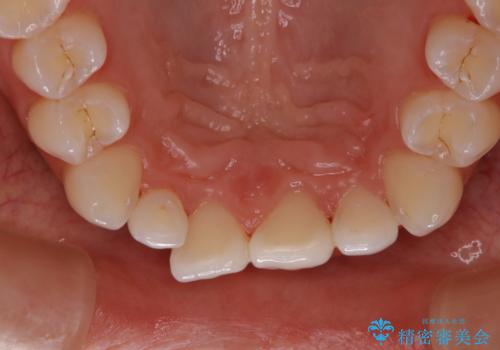

前歯のかぶせ物の色があっていない オールセラミック治療